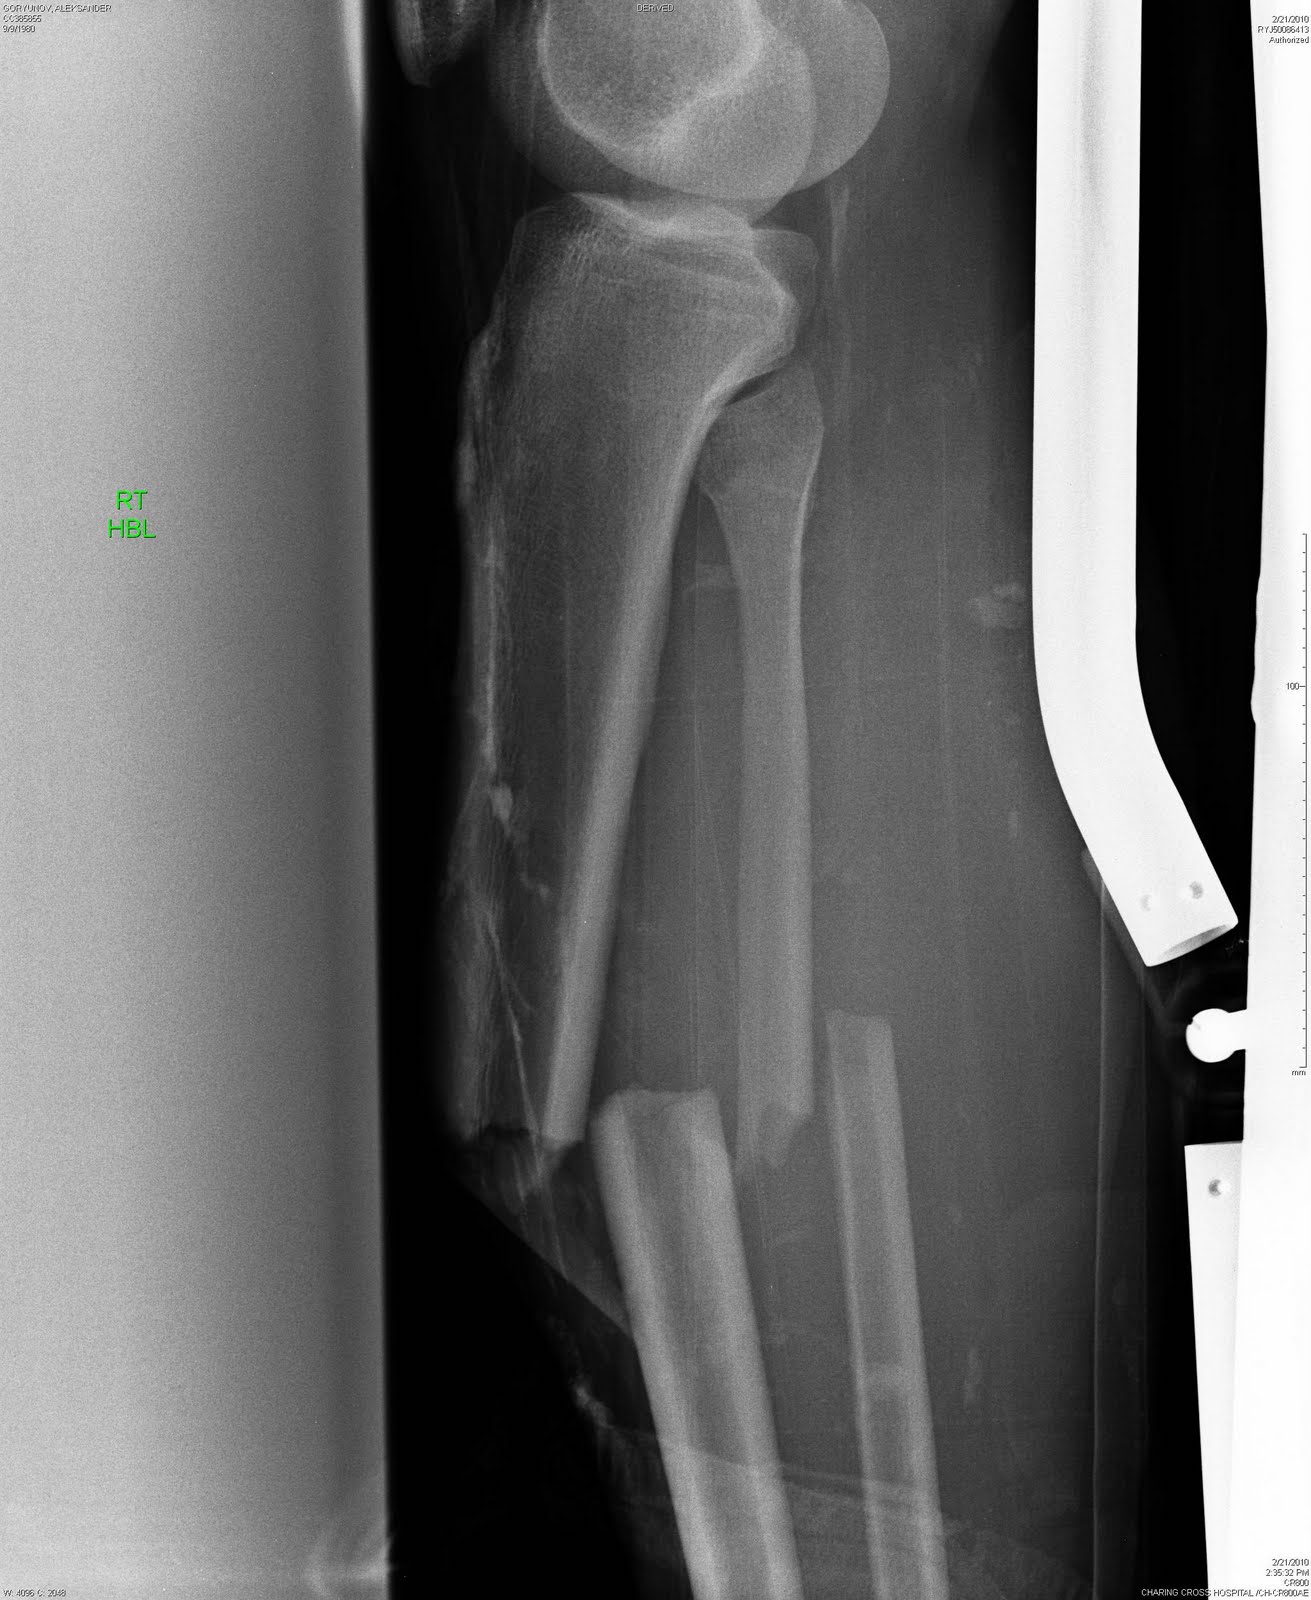

Ну, а во время операции под коленом внутрь кости вводят титановый стержень (длина - 40см, диаметр - 12 мм), который фиксируется парой винтов над лодыжкой и парой под коленом. Через год, весь этот металлолом можно вытащить обратно (что я и собираюсь сделать летом 2011-го). Операция нынче достаточно стандартная, только у меня немного осложненная выбитом на колени "клином", так что "ковырялись" в ноге не полтора часа, а три. Без гипса. С некоторыми деталями я уже был знаком - 2 года назад ошибся на выходе и сломал ногу нападающему. У него перелом был "чище" моего. А мне - карма. Результат вот такой.